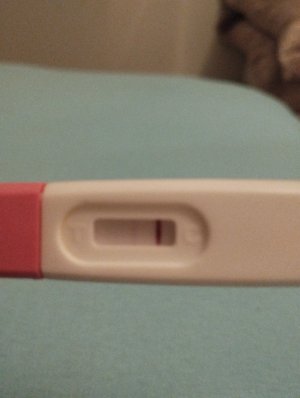

Merhaba kızlar ben reglme 2 gün kala erken gebelik testi yaptım silik çizgi çıktı snra emin olmak için bir tane daha yaptım oda silik cıktı bu gun regl gunum olmadım gittim normal gecelik testi yaptım onda da çok silik çizgi cıktı sizdn fikir almak istiyorum sizce var mı testleri buraya koycam karartma yaptım

Erken gebelik testi